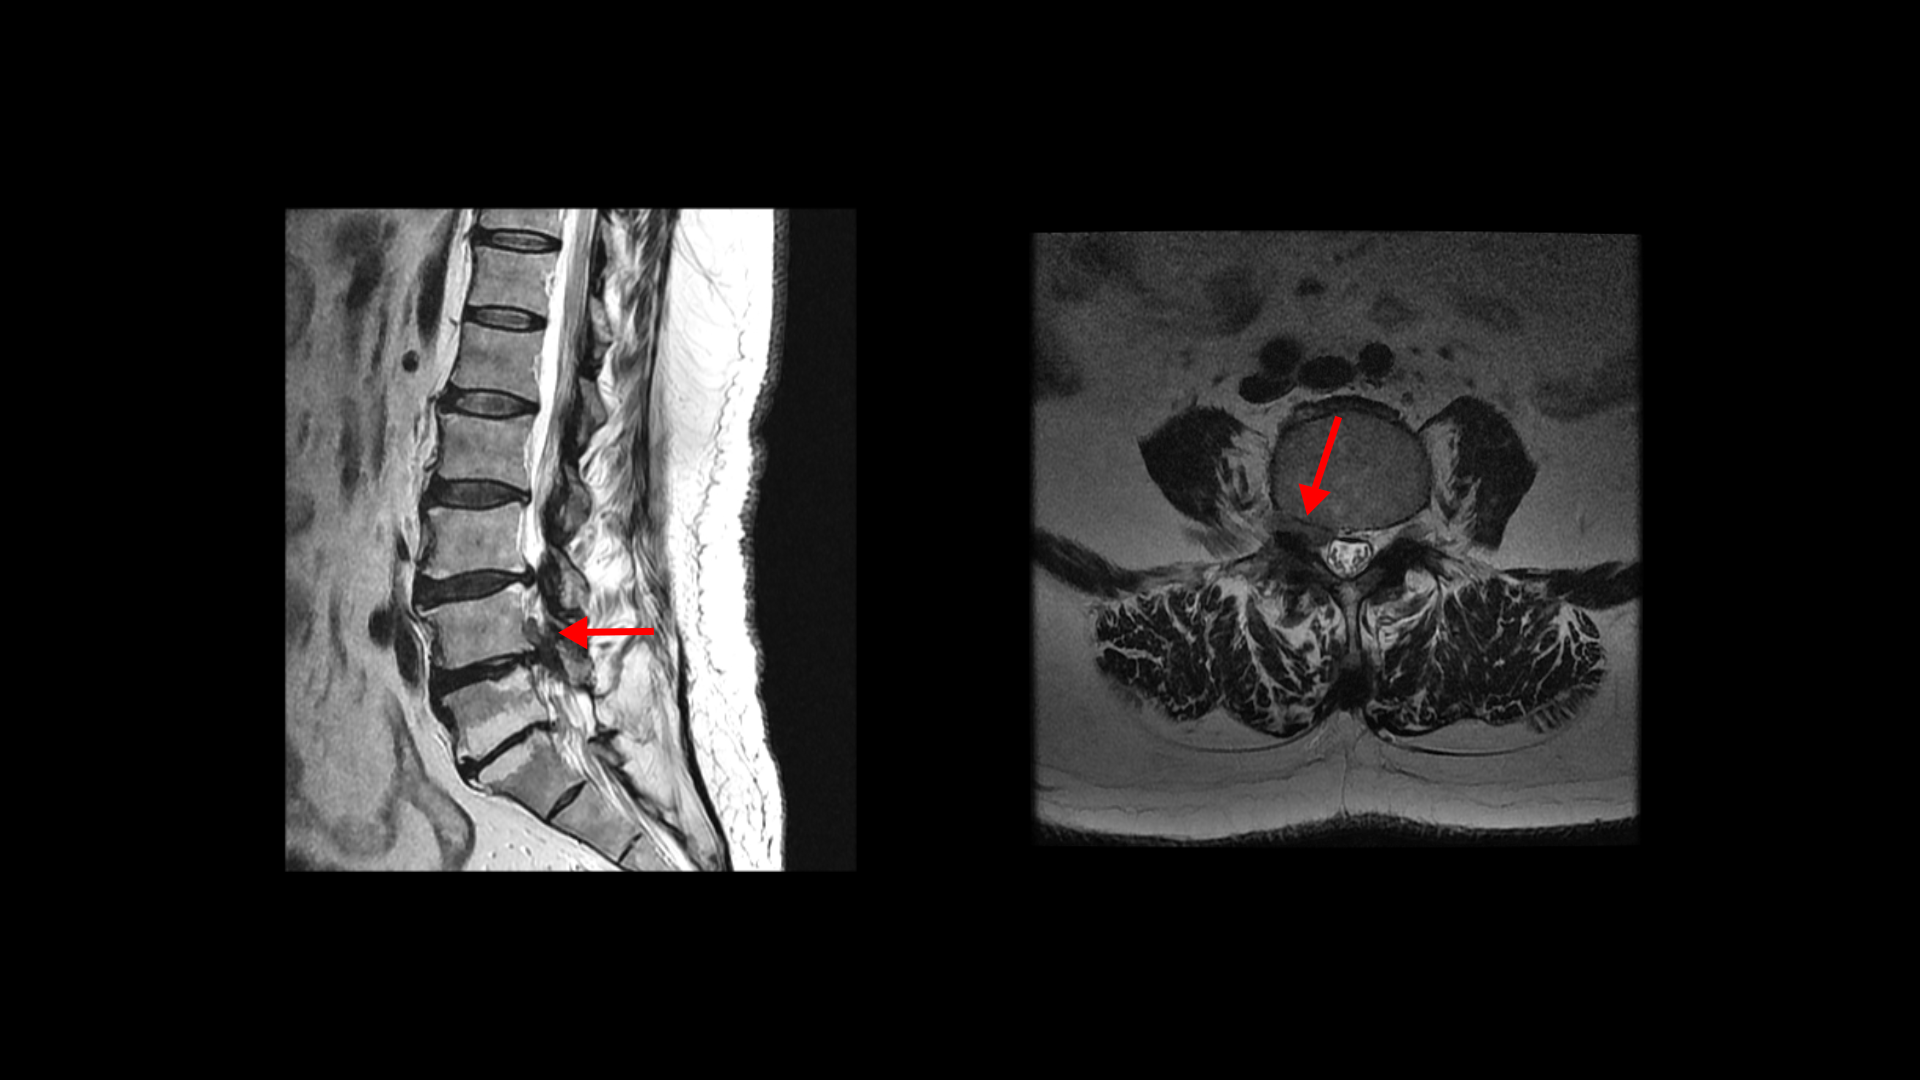

이 환자분은 허리수술을 여러 번 한 상태에서 결국에는 척추유합술까지 하셨습니다. MRI를 보시면 5번 1번 후궁에 수술한 자국이 보입니다.

4번 5번 후궁 양쪽으로 수술한 자국이 보입니다.

올해 초에 4번 5번 디스크가 또 오른쪽으로 심하게 파열돼서 결국 후궁과 후관절, 황색인대를 모두 다 제거하고 나사를 박는 척추유합술을 하셨습니다.

그런데 척추유합술을 하고 난 후 오른쪽 다리의 증상은 호전되었으나 상대적으로 증상이 괜찮았던 왼쪽 다리에 심한 방사통과 마비 증상을 호소하셨습니다. 수술한 병원의 집도의로부터 수술은 잘 됐으나 수술한 자리가 부어있기 때문에 신경을 눌러서 그런 거라고 1년 이상 기다리면 회복될 것이라는 얘기를 들으셨다고 합니다.